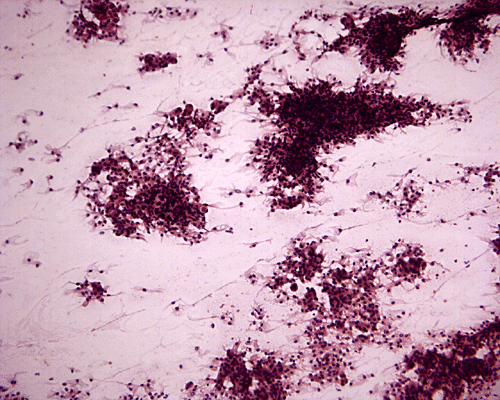

On cytologic preparation, there are irregular clusters of cells and in between these clusters are many single cells (Panel F). The background is clean and if free of mitosis. On high-magnification, some of these cells are arranged in small concentric whorls (ß in Panel G). Pseudonuclear inclusion can be seen in some nuclei (ß in Panel G). The cytoplasm of these cells seems to be triangular, pointy, well defined and finely granular. Quite some clusters of cells with gigantic "bubbles " several times the size of the nucleus containing eosinophilic cores with a halo are present (Panel H). On frozen section, the tumor cells arrange in solid sheets with many microcysts in between. Many of the smaller microcysts contain a eosinophilic, amorphous core that correspond to the giant "bubbles" on the cytologic preparation (Panel I). On high-magnification, the cells have epithelioid appearance with pseudonuclear inclusion in many nuclei (Panel J). These features are highly suggestive of a secretary meningioma. The main differential diagnosis in this case is metastatic adenocarcinoma. Although the gigantic "bubbles" suggest mucin secretory adenocarcinoma, the cytoplasmic vacuoles rare approach the size of several times that of the nuclei as illustrated in this case. Besides, necrosis is often present in metastatic adenocarcinoma.  [Click here to see a mucin producing adenocarcinoma in cytologic preparation] [Click here to compare the cytologic preparation of a metastatic renal cell carcinoma] The large amount of edema on MRI also raises the suspicion of metastatic adenocarcinoma. It should be noted that secretory meningiomas are typically associated with a disproportionally extensive edema.